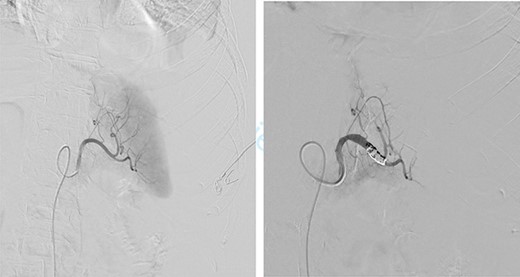

First, we embolized the splenic artery with coils (Fig. 3). The patient was getting well at intensive unit care, but few hours after embolization, she was shocked again.